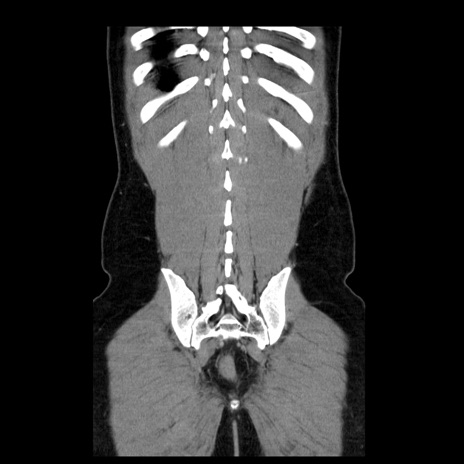

症例4(冠状断像)

【症例】30歳代男性

【主訴】腹痛、嘔吐

【現病歴】昨晩から突然の腹痛あり、その後嘔吐、軟便も出現。腹痛が改善しないため救急搬送となる。2日前にしめ鯖の食事歴あり。

【身体所見】意識清明、苦悶様、BP 135/90mmHg、BT 35.7℃、腹部:平坦、やや硬、心窩部〜臍部に自発痛、圧痛あり、筋性防御+、反跳痛-

【データ】WBC 8100、CRP 0.57